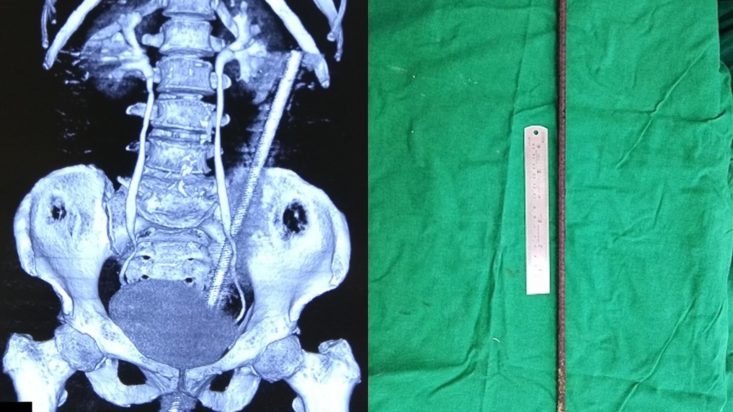

Η γυναίκα βρισκόταν στο χωράφι που βρίσκεται δίπλα στο σπίτι της, φροντίζοντας τις αγελάδες της, όταν η μοίρα της έπαιξε ένα τρομακτικό παιχνίδι. Μία σκουριασμένη μεταλλική βέργα, μήκους σχεδόν 60 εκατοστών, είχε τοποθετεί στο έδαφος του χωραφιού, προκειμένου να στηρίξει αναρριχώμενα φυτά. Η γυναίκα, ενώ φρόντιζε τις αγελάδες της, έχασε την ισορροπία της λόγω της «ανησυχίας» μιας αγελάδας, καθώς ήταν δεμένη μαζί της με ένα σχοινί στον καρπό της, και κάθισε επάνω στη βέργα, με αποτέλεσμα να εισέλθει από τον πρωκτό της, να διαπεράσει το έντερό της και να επεκταθεί πίσω από την κοιλιακή κοιλότητα.

Η κατάσταση της γυναίκας ήταν σοβαρή, καθώς η βέργα είχε προκαλέσει διάτρηση του εντέρου και είχε εισχωρήσει στον χώρο πίσω από την κοιλιακή κοιλότητα. Παρά τη σοβαρότητα του ατυχήματος, η βέργα δεν κατάφερε να προκαλέσει βλάβες σε αιμοφόρα αγγεία και ζωτικά όργανα, κάτι που αναφέρθηκε στην ιατρική έκθεση για την περίπτωση της.

Η χειρουργική επέμβαση, που διήρκεσε δύο ώρες, περιλάμβανε την αφαίρεση της ράβδου μέσω του πρωκτού και την αποκατάσταση της διάτρησης. Μετά την επέμβαση, η γυναίκα είχε ναυτία και κοιλιακούς πόνους ενώ δεν μπορούσε να περπατήσει. Ωστόσο, η ανάρρωσή της προχώρησε χωρίς προβλήματα και, μετά από περίπου δέκα ημέρες, κατάφερε να επιστρέψει στο σπίτι της.